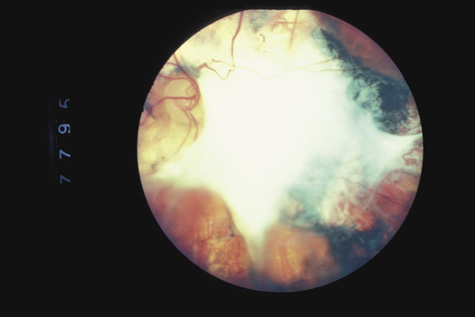

RETINAL DETACHMENT

Because men and boys are most likely to be engaged in fighting or contact sports, it is not surprising that at least three-fourths of the patients with traumatic retinal detachment are men or boys,84 and that blunt trauma is the leading cause of retinal detachment in children and adolescents.85 Because the affected patients have a formed vitreous, traumatic retinal detachments typically progress slowly unless a giant tear is present. In some patients, the trauma occurs months or years before the detachment is diagnosed. Demarcation lines, atrophy of the underlying pigment epithelium, subretinal precipitates, retinal macrocysts, and extensive vitreous “tobacco dust” are all commonly seen (Fig. 18). Proliferative vitreoretinopathy is uncommon, so the prognosis for reattachment is excellent, provided, of course, that all breaks are found. In 87% of traumatic retinal detachments, the causative tear is found at the vitreous base. Superonasal breaks at the anterior vitreous base are commonly overlooked. Because many traumatic retinal breaks cause subsequent retinal detachment, they should all be treated with laser or cryotherapy.

Fig. 18. A typical traumatic retinal detachment. There is an inferotemporal retinal dialysis, a demarcation line, and no signs of proliferative vitreoretinopathy.